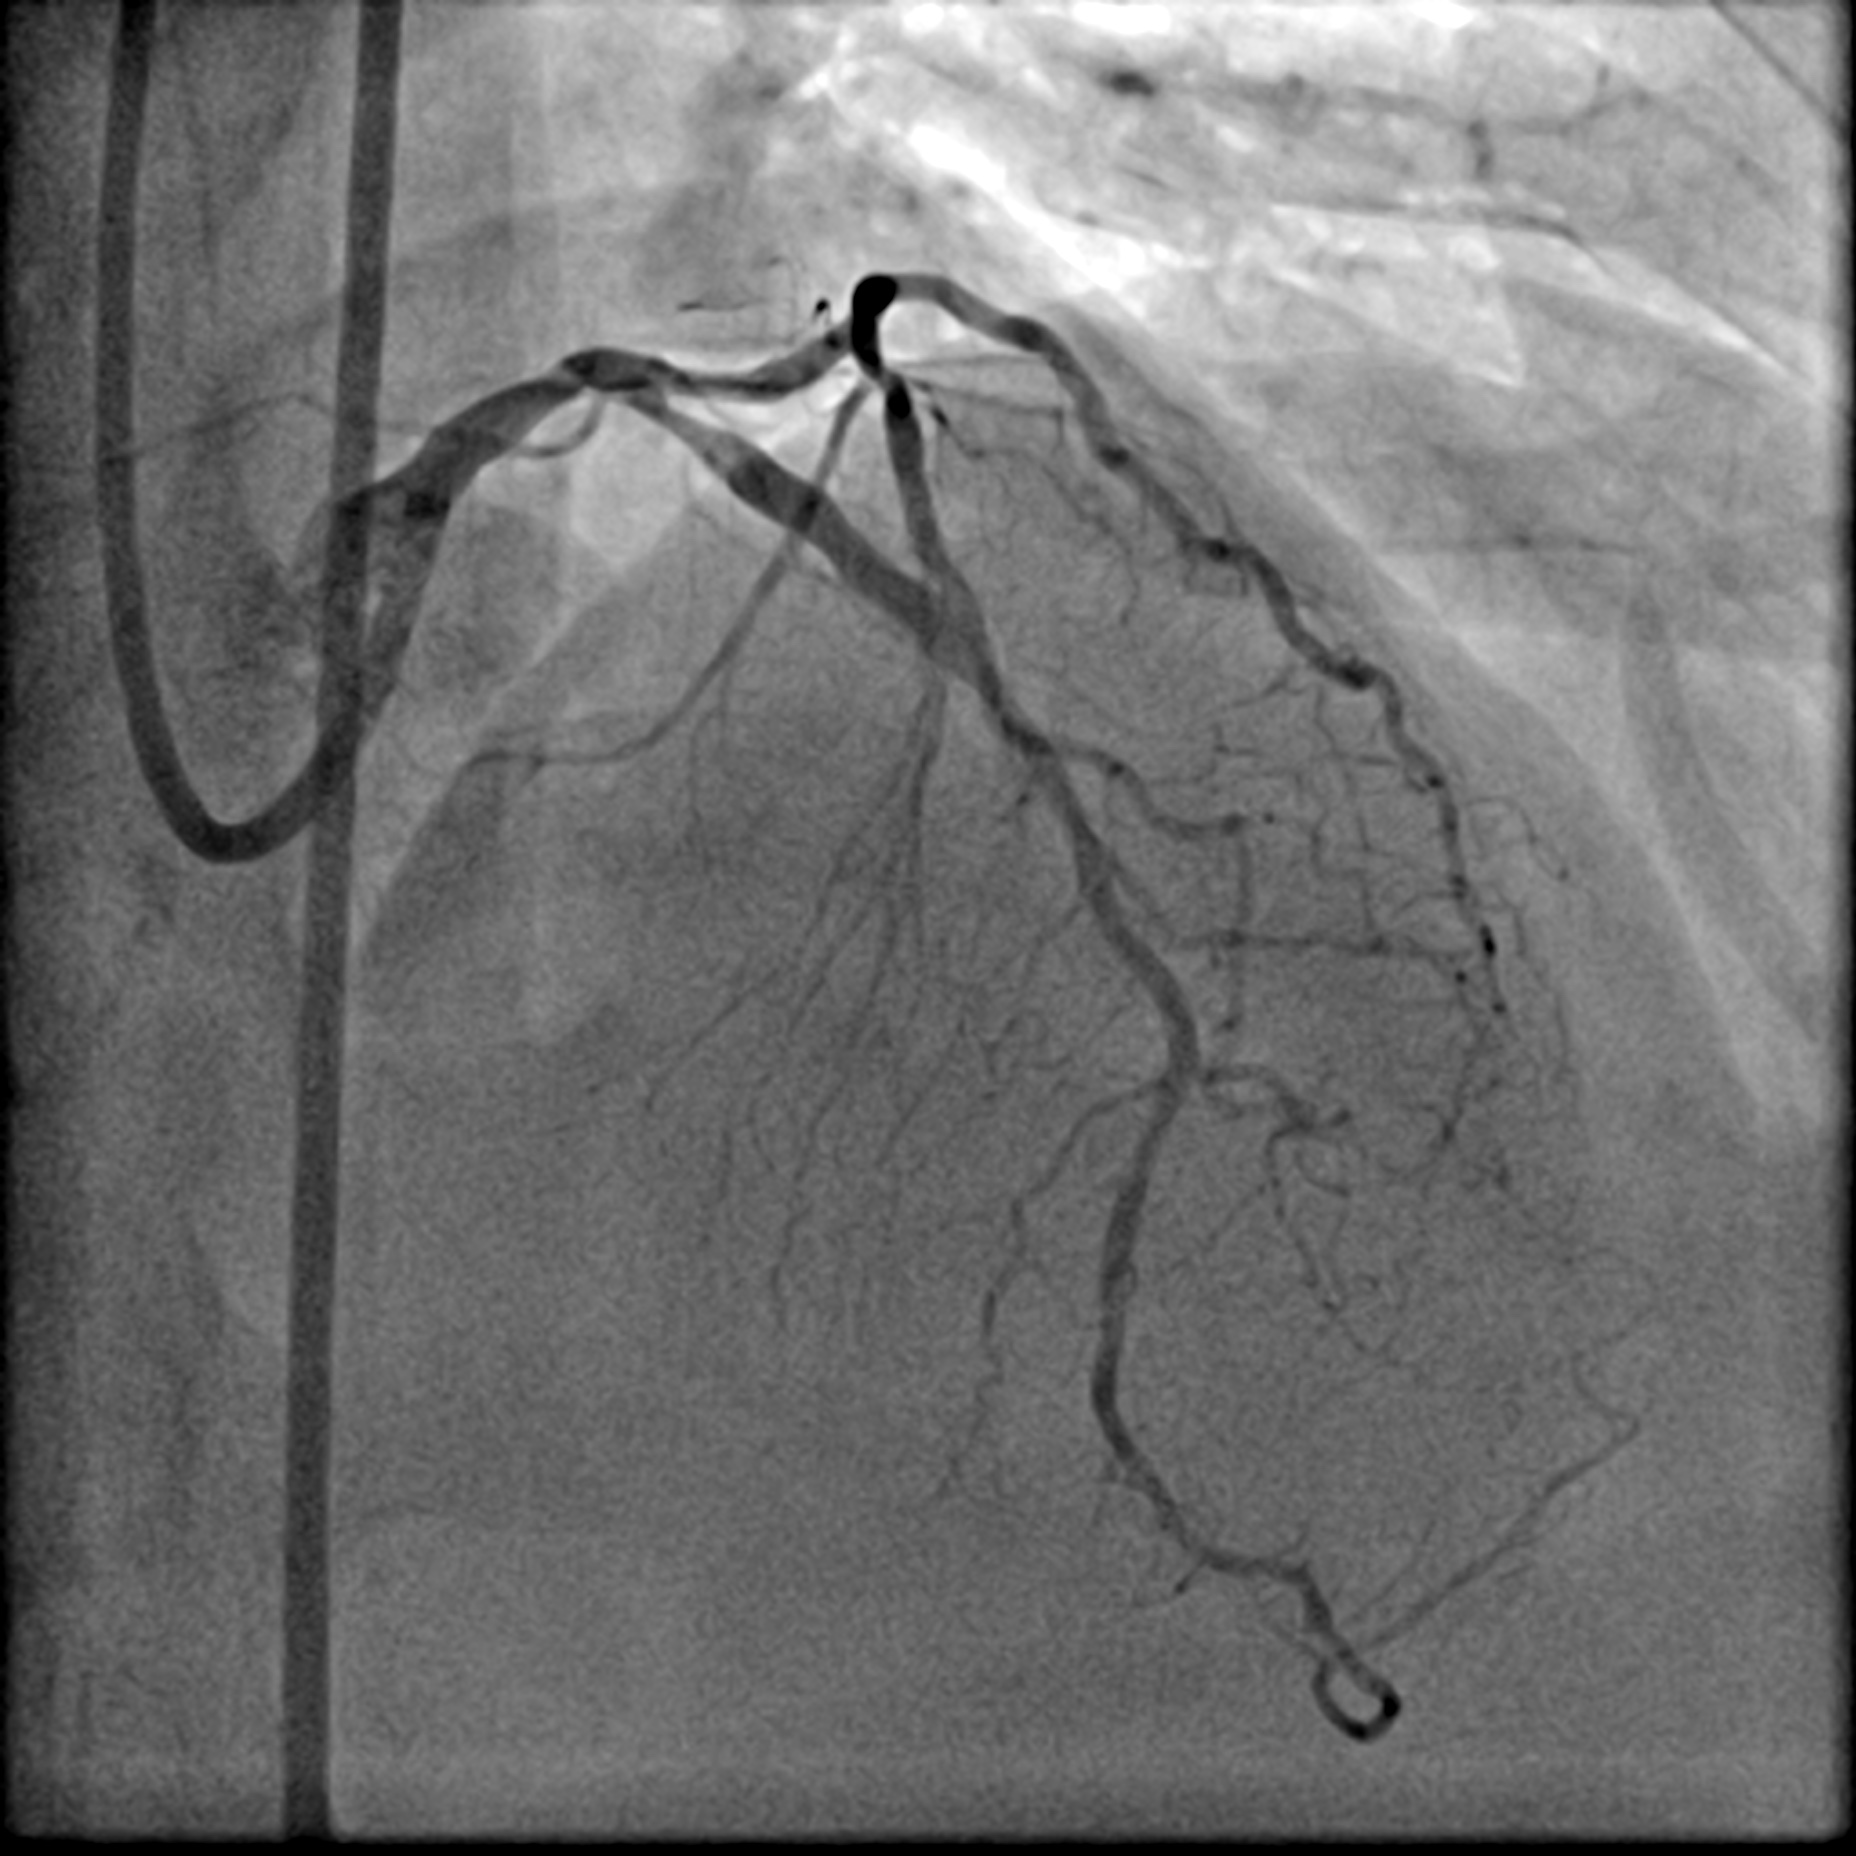

Relevant Catheterization Findings

The Right Coronary Artery only had mild disease. There was a Left Main Stem (LMS) bifurcation lesion involving the ostium of the Left Anterior Descending (LAD) artery and the Left Circumflex (LCx) artery (Medina 1,1,1). A conspicuous calcification was visible on fluoroscopy. Intravascular Ultrasound (IVUS) was utilized to further assess the lesion. Its findings correlated with those from fluoroscopy. Specifically, a calcium nodule was identified at the ostium of the LCx in the anti-carina area.